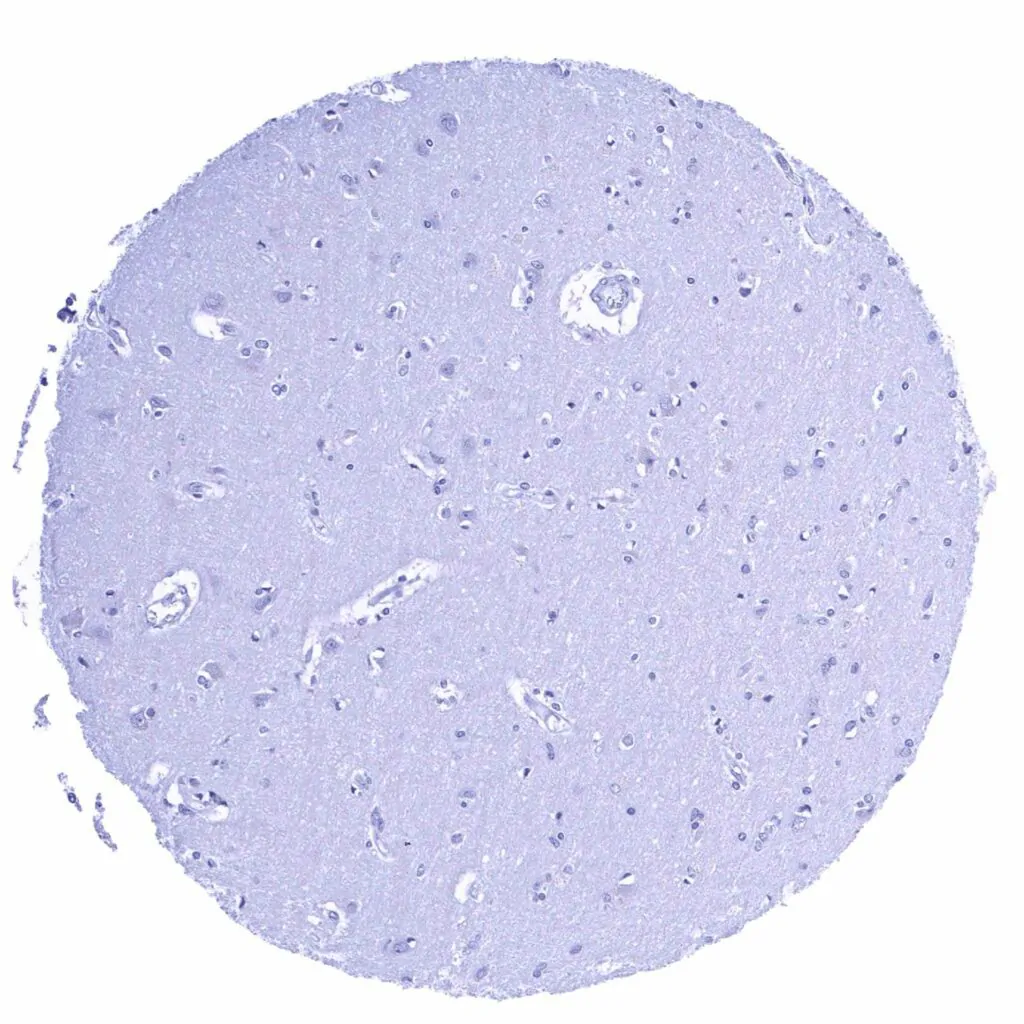

Cerebrum, grey matter